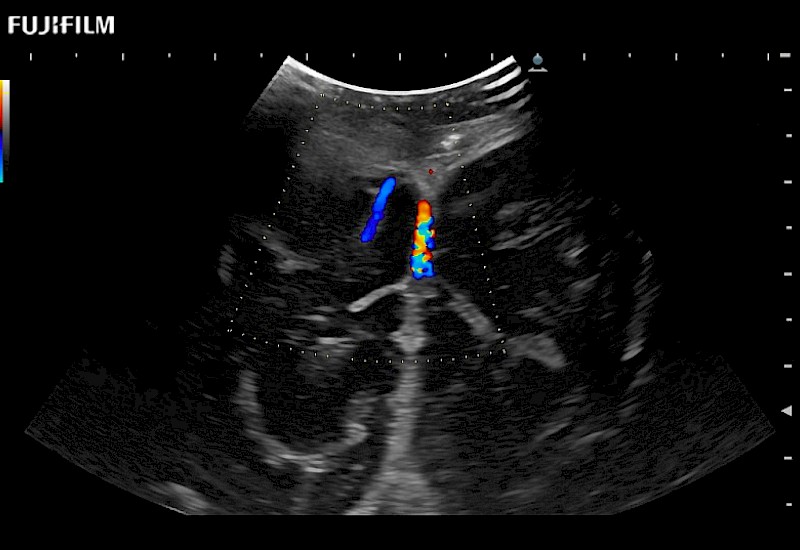

Extraordinary high-resolution digital imaging

Exceptional transducers

Multi-Parametric imaging modalities